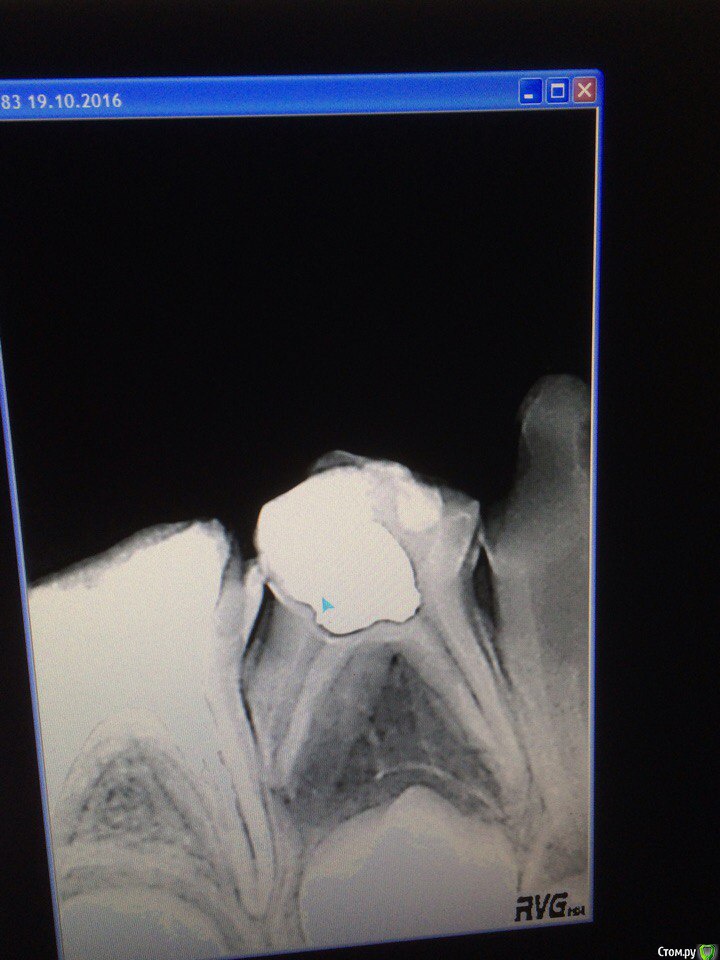

Wrestrus66 Опубликовано 23 октября, 2016 Поделиться Опубликовано 23 октября, 2016 Всем привет..Пациент: 6.5 годаЖалоб нет..Что делать с 84 зубом так оставить или же удалять? ( но вот в чём проблема ей удалил 83 от того что боковой резец упирался прям в клыл и ему место не было)Зуб со свищем + дистальная резорбция..Лечить или же так и оставить?У кого какие идеи?! Ссылка на комментарий

crown Опубликовано 23 октября, 2016 Поделиться Опубликовано 23 октября, 2016 Отлично, теперь не будет места клыку. Проблемы с прикусом - отправляйте к ортондонту. А что такое дистальная резорбция? Ссылка на комментарий

Kota Опубликовано 23 октября, 2016 Поделиться Опубликовано 23 октября, 2016 попробуйте все таки запломбировать каналы кальцием. может и уйдет воспаление. удалить всегда успеете. 2 Ссылка на комментарий